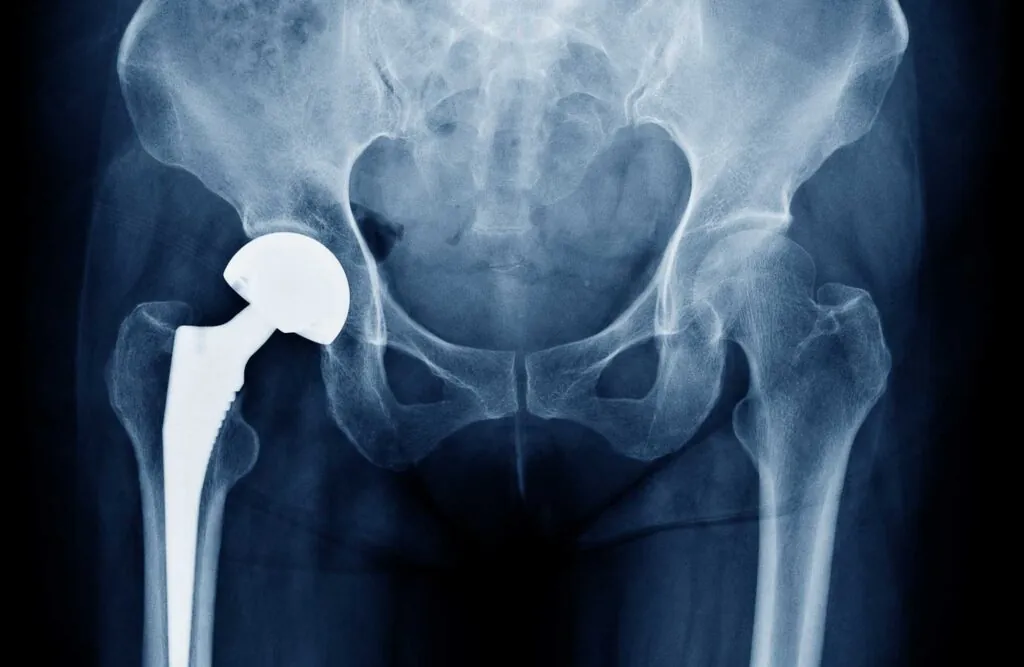

Hip Replacement Operation in Bangladesh, also called Total Hip Arthroplasty (THA), is a procedure where a damaged hip joint is replaced with an artificial implant made of metal, ceramic, or plastic components.

The hip joint is a ball-and-socket joint. When cartilage wears away due to arthritis or injury, it causes severe pain and stiffness. Hip replacement surgery removes the damaged bone and cartilage and replaces it with prosthetic components to restore movement and relieve pain.

- Total Hip Replacement (THR) – Both ball and socket replaced

- Partial Hip Replacement – Only the ball part replaced

The damaged cartilage and bone are removed. - Implant Placement

- Metal stem inserted into thigh bone

- Artificial ball placed on stem

- Socket replaced with artificial cup